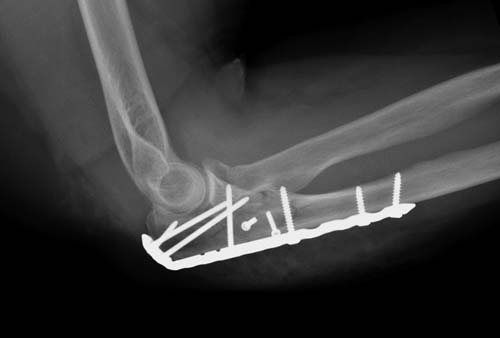

Здесь представлены несколько случаев и как видно больше больных с

серьезными повреждениями, чем изолированные..

В первом случае перелом Монтеджи, где доперационно сделано оценка

положения головки к остальным элементам под рентгеном. Учитывая

правильность взаимотношении произведена фиксация только локтевого

отростка, Второй случай, заменена на протез, и третий, кроме фиксации

головки - реконструкция capitellum латерального мыщелка.